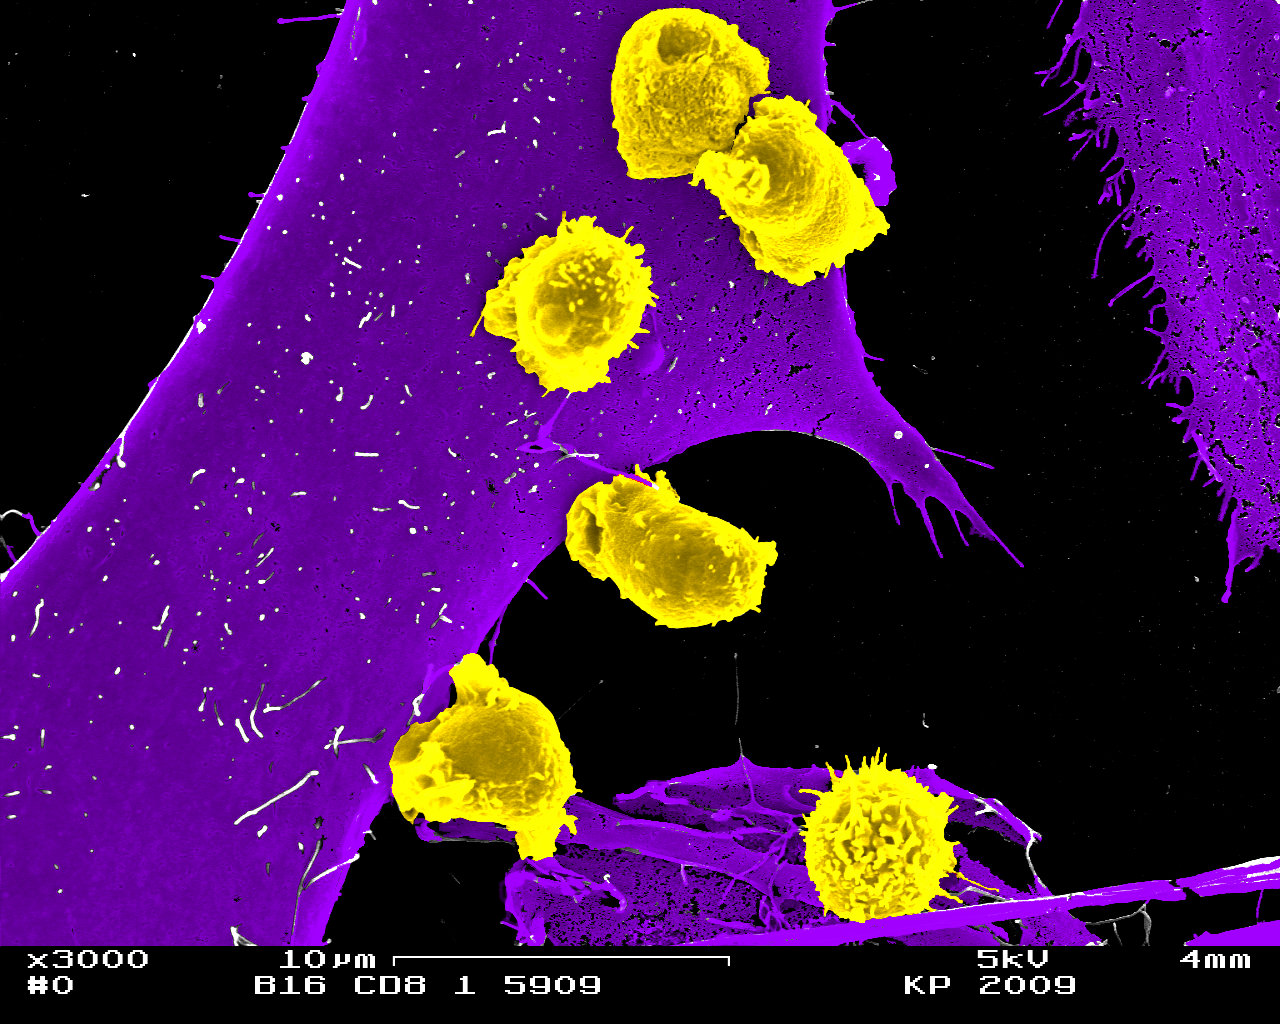

Innsbruck, am 3. Juli 2023: Vor zehn Jahren wurden die ersten Leukämiepatient:innen mit chimären Antigenrezeptor (CAR) exprimierenden T-Zellen behandelt. Ein Jahrzehnt später sind viele der Betroffenen noch immer ohne Krankheitssymptome. Im Rahmen dieser innovativen CAR-T-Zell-Therapie werden bestimmte Immunzellen, die T-Zellen, aus dem Blut der Patient:innen gewonnen und in der Folge gentechnisch aufgerüstet und den Patient:innen über eine Infusion wieder zugeführt. Die mit einem Tumorerkennungsrezeptor ausgestatteten CAR-T-Zellen sind in der Lage, Tumorzellen gezielt zu erkennen, an diese anzudocken und sie zu zerstören. Bei schwer behandelbaren soliden Krebserkrankungen wie dem nicht-kleinzelligen Lungenkarzinom (NSCLC) blieb jegliche Wirksamkeit von CAR-T-Zellen bislang jedoch aus.

Mit der Blockade von Immun-Checkpoint Molekülen in CAR-T-Zellen könnte sich nun eine vielversprechende Therapieoption eröffnen, die tumorzellschädigende Funktion der schon heute verfügbaren CAR-T Zellen am Ort des soliden Tumors entscheidend zu verbessern. Solcherart hergestellte Zellen könnten ein potenziell effektives „lebendes Medikament“ zur Abtötung von Tumorzellen auch in der immunsuppressiven Tumorumgebung darstellen. Genau diesen Weg wollen Gottfried Baier und invIOs in einem neuen, von der FFG geförderten BRIDGE*-Projekt (Extension of CD8 CAR-T cell therapy success by CBLB pathway blockade; Acronym „EXCEL-T“) beschreiten.

„Wir wollen die Wirksamkeit von CAR-T Immunzelltherapie speziell bei soliden Tumoren wie NSCLC wesentlich und bestmöglich verstärken, und gleichzeitig mittels des patienteneigenen Immunsystems die Anti-Tumorimmunität ankurbeln und bisher beobachtete Therapieresistenzen langfristig vermeiden“, beschreibt Gottfried Baier das gemeinsame Projektziel.